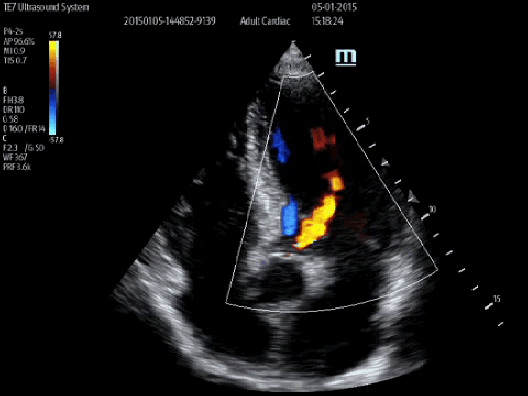

Smart Track

Dzięki zastosowaniu inteligentnego wykrywania naczyń krwionośnych, aparat może automatycznie optymalizować obraz Kolorowego i Power Dopplera oraz położenie bramki i spektrum Dopplera PW, żeby zredukować powtarzalne i czasochłonne działania i uprościć badanie naczyń krwionośnych